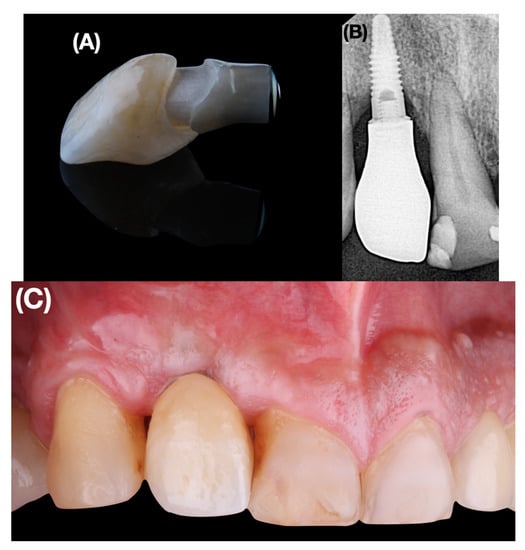

Clinical examination showed generalized inflammation with increased probing depths (Figure 1A). In the area of implant 1.2, the reason for which the patient came to the Master’s office, a PSTD associated with loss of the mesial and distal papilla was observed (Figure 1B).

Figure 1.

(A) Clinical and periodontal examination. (B): Preoperative intraoral view. (C): Occlusal view without implant crown. The head of the implant is inside the straight imaginary line that connects the profile of the adjacent teeth at the level of the gingival margin. (D): Occlusal view. The crown profile is located outside the imaginary curve line that connects the profile of the adjacent teeth at the soft tissue margin. (E): Baseline clinical aspect of buccal soft tissue dehiscence and lack of peri-implant papilla.

From the esthetic point of view, the initial PES index with the temporary implant-supported crown was 0 points and the initial WES was 1 point (Table 2).

Also, a gray shade was observed in the vestibular soft tissue of the implant. The position of the implant head 12 was located within (more palatally) the straight imaginary line connecting the profile of the adjacent teeth at the level of the gingival margin (Figure 1C). After placement of a screw-retained temporary crown on implant 1.2, it was observed that the profile of the temporary crown was outside (more vestibular) of the imaginary curved line connecting the profile of the adjacent teeth at the level of the soft tissue margin (Figure 1D). The height of both the mesial and distal papillae were more apical than the esthetically ideal position of the soft tissue margin of the implant-supported crown (Figure 1E). Therefore, the defect could be defined according to the classification proposed by Zucchelli et al. [] as class III, subclass C.

In the evaluation by cone beam computed tomography, the implant presented an inadequate angulation in addition to an almost inappreciable facial bone wall and an incorrect position in the apico-coronal direction as it was too deep (Figure 2A). The periapical radiograph showed bone and attachment loss in both the implant and the adjacent natural teeth 1.1 and 1.3 (Figure 2B).

Figure 2.

(A): Cone beam computed tomography. (B): Intraoral periapical radiograph.